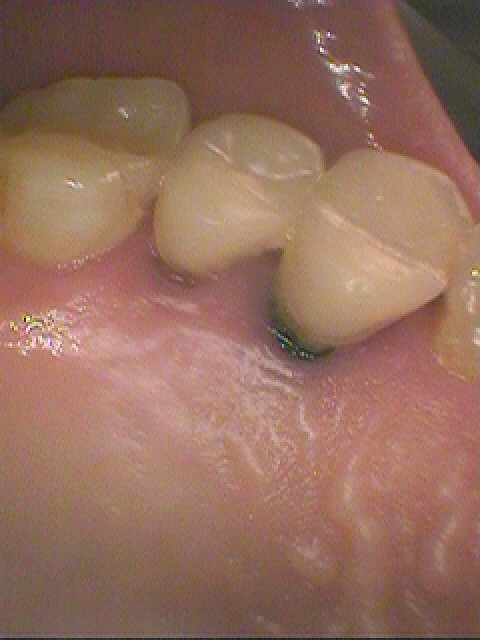

右上4番、抜歯即時インプラント埋入へ。| |広島市安佐南区の歯科医院 右上4番、抜歯即時インプラント埋入へ。 トップ お知らせ・ブログ 右上4番、抜歯即時インプラント埋入へ。 右上4番、抜歯即時インプラント埋入へ。 Web診療予約 初めての方へ 選ばれ続ける理由 院内設備について 歯が痛いしみる一般歯科 歯がぐらぐらする歯周病 健康な歯を保ちたい予防歯科 子供の虫歯予防をしたい小児歯科 銀歯をセラミックに審美歯科 白い歯を目指しませんか?ホワイトニング 矯正専門医がいるので安心矯正歯科 抜けた歯を補いたいインプラント・入れ歯 医院案内 スタッフ紹介 メリィハウス歯科クリニックオフィシャルホームページ ラベンダー歯科クリニックオフィシャルホームページ お知らせ・ブログ ホーム 診療科目 一般歯科 歯周病治療 予防治療 小児歯科 審美治療 ホワイトニング 矯正歯科 入れ歯・インプラント マウスピース矯正 初めての方へ 院長・スタッフ 設備紹介 医院案内・アクセス メニューを閉じる